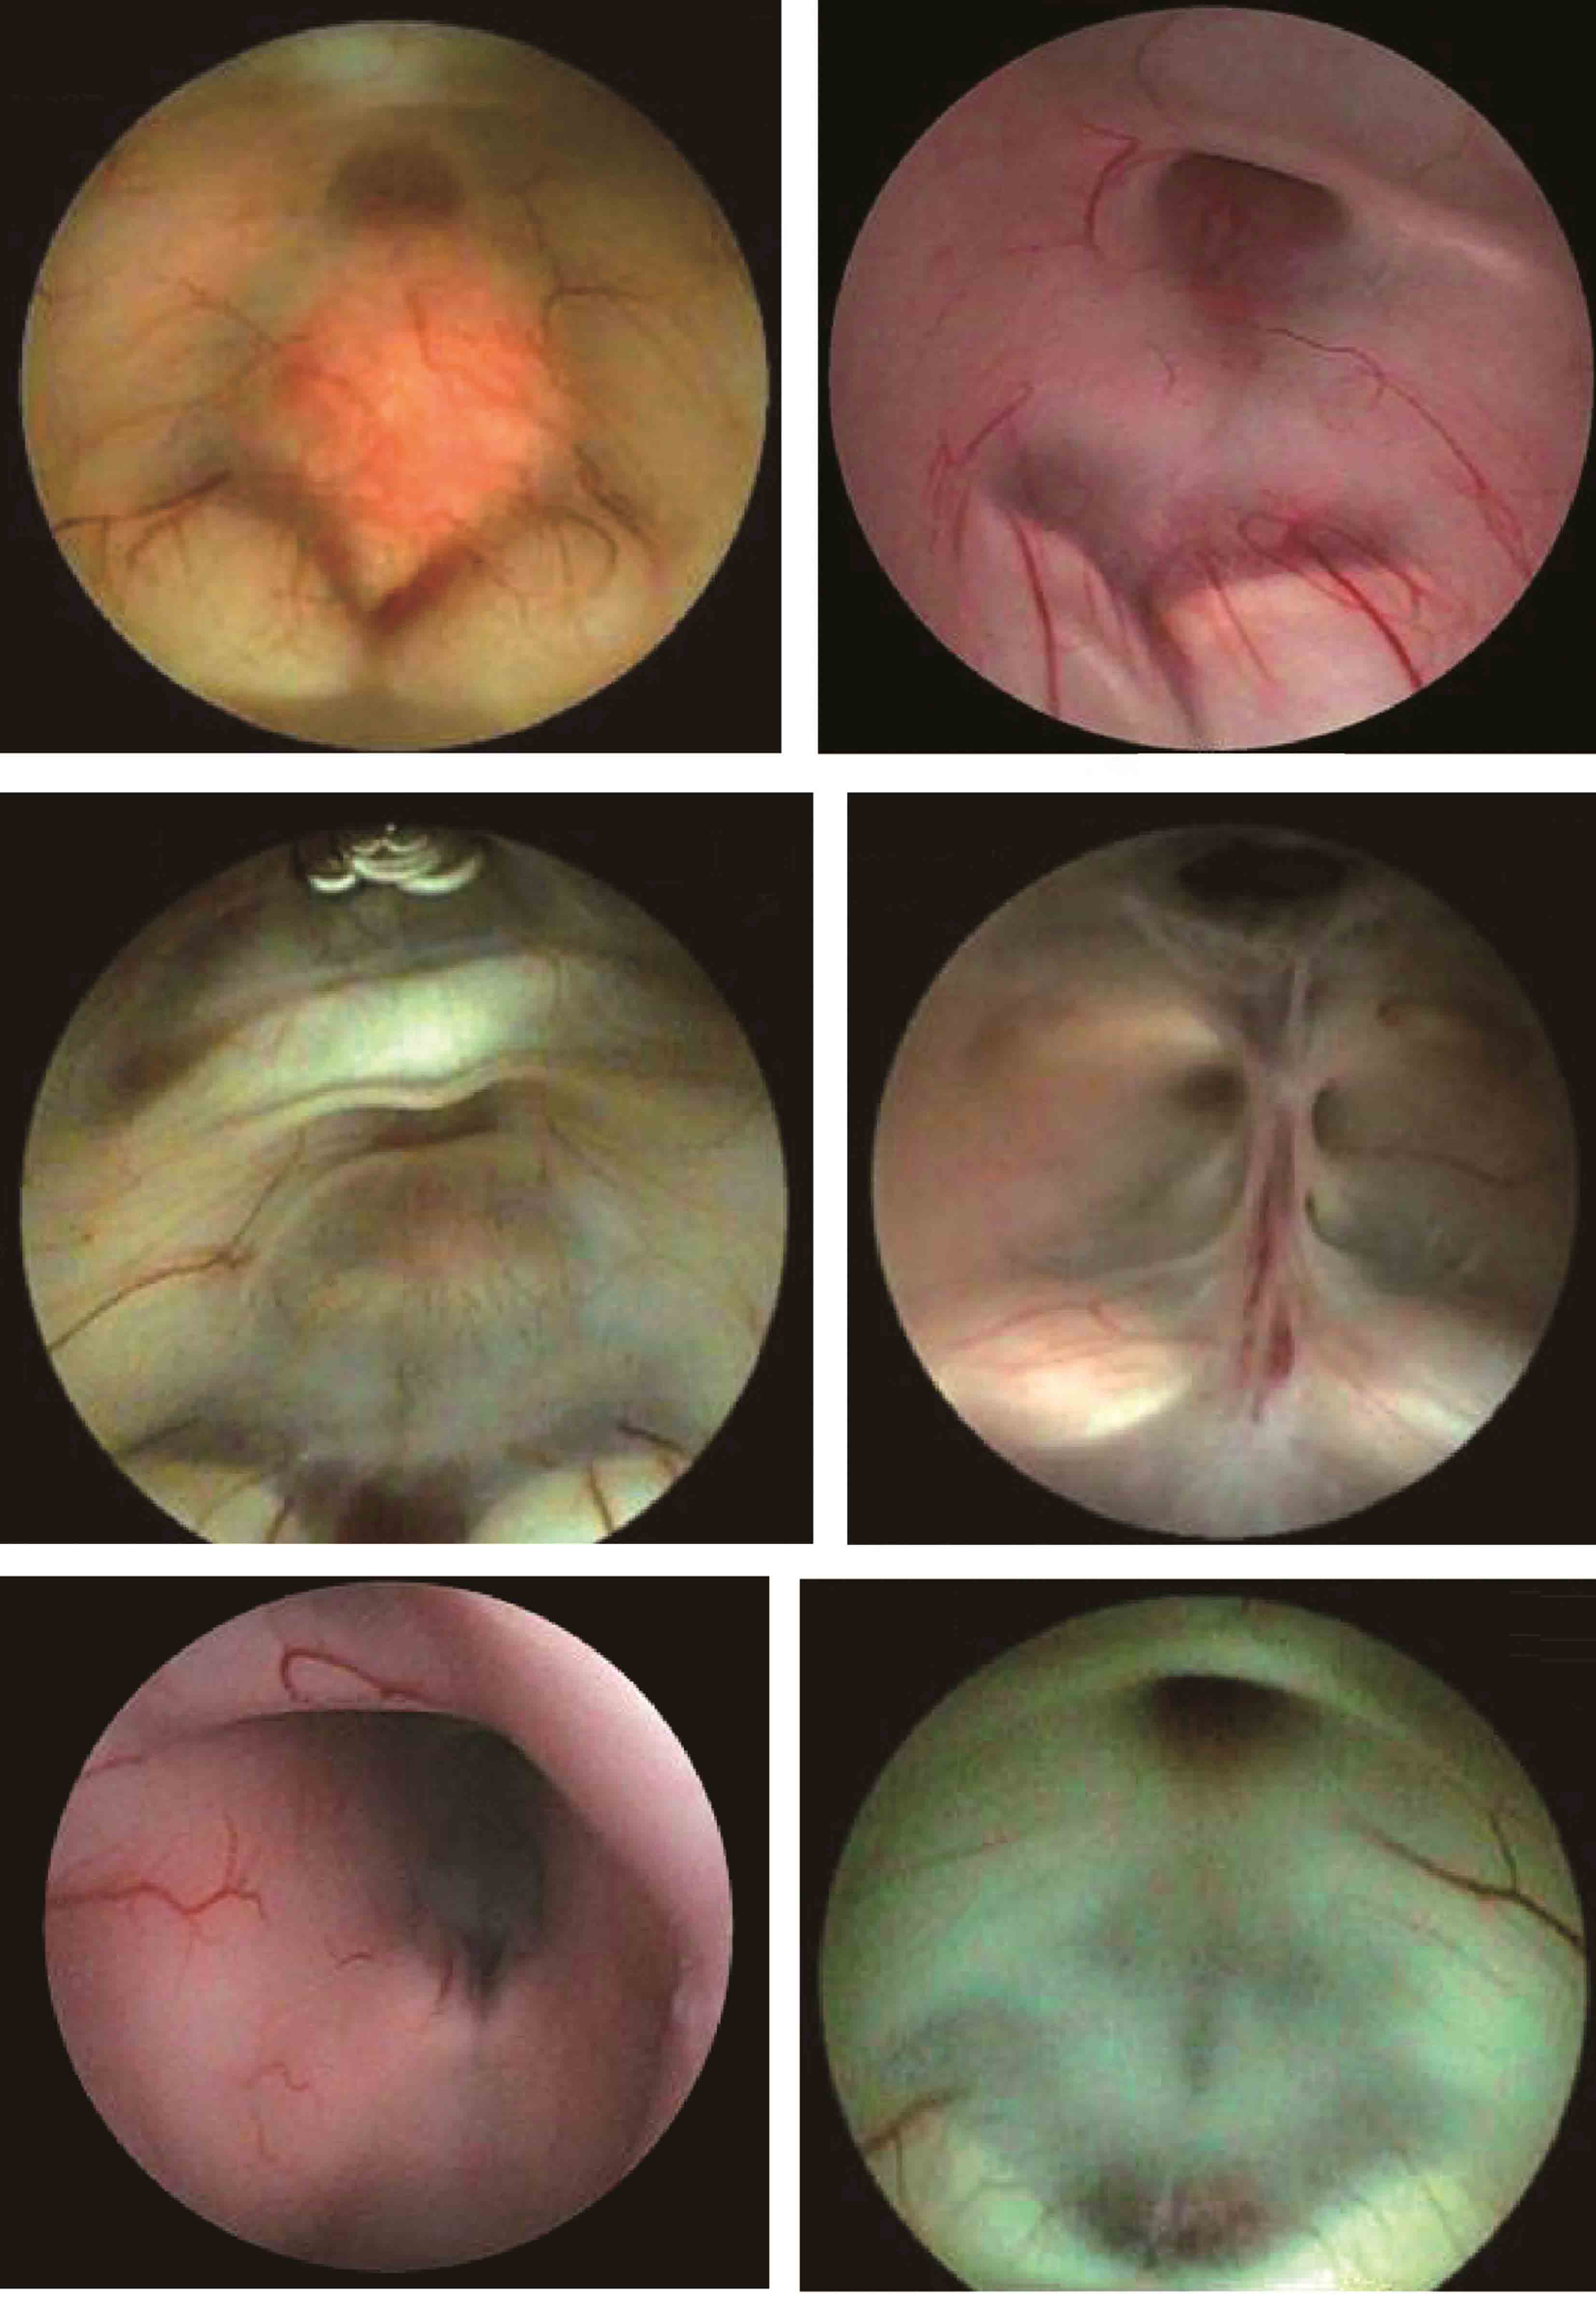

图3-1-1-4 感染后脑积水内镜下探查所见

a.脑室壁上的菌斑;b.脑室内结核所致干酪样坏死物;c.脑室内真菌感染;d.第四脑室内囊虫